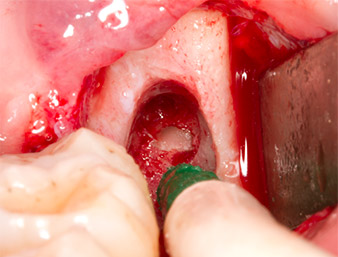

The tissue above the root remnant was not completely ossified and consisted for the most part of granulation tissue modified by inflammation (Fig. 4).

Granulation tissue

Fig. 4: Two Langenbeck retractors and a raspatorium expose the operating area. Granulation tissue of the incompletely healed first osteotomy can be seen.